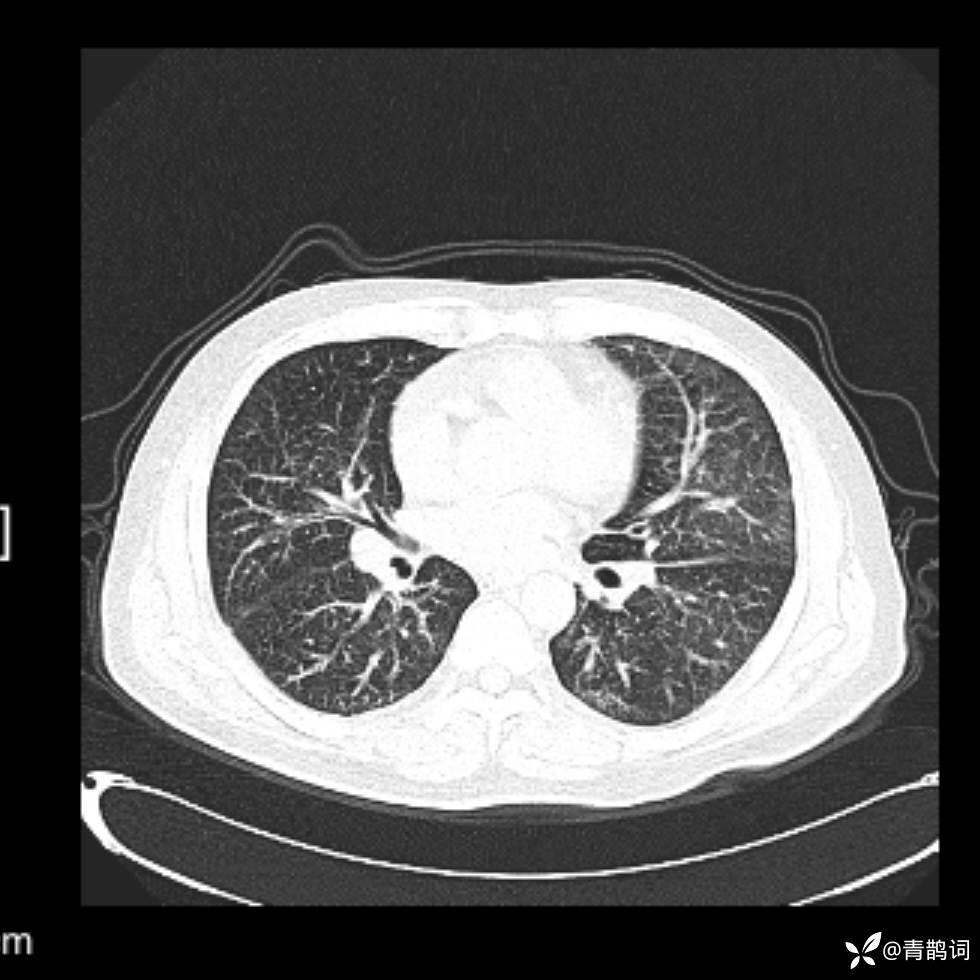

患者年龄:30岁。

患者性别:男。

简要病史:左颜面部肿胀2年,反复咳嗽咳痰,逐渐加重。

辅助检查

结合病史及影像学表现,期待评论区各位老师各抒己见~